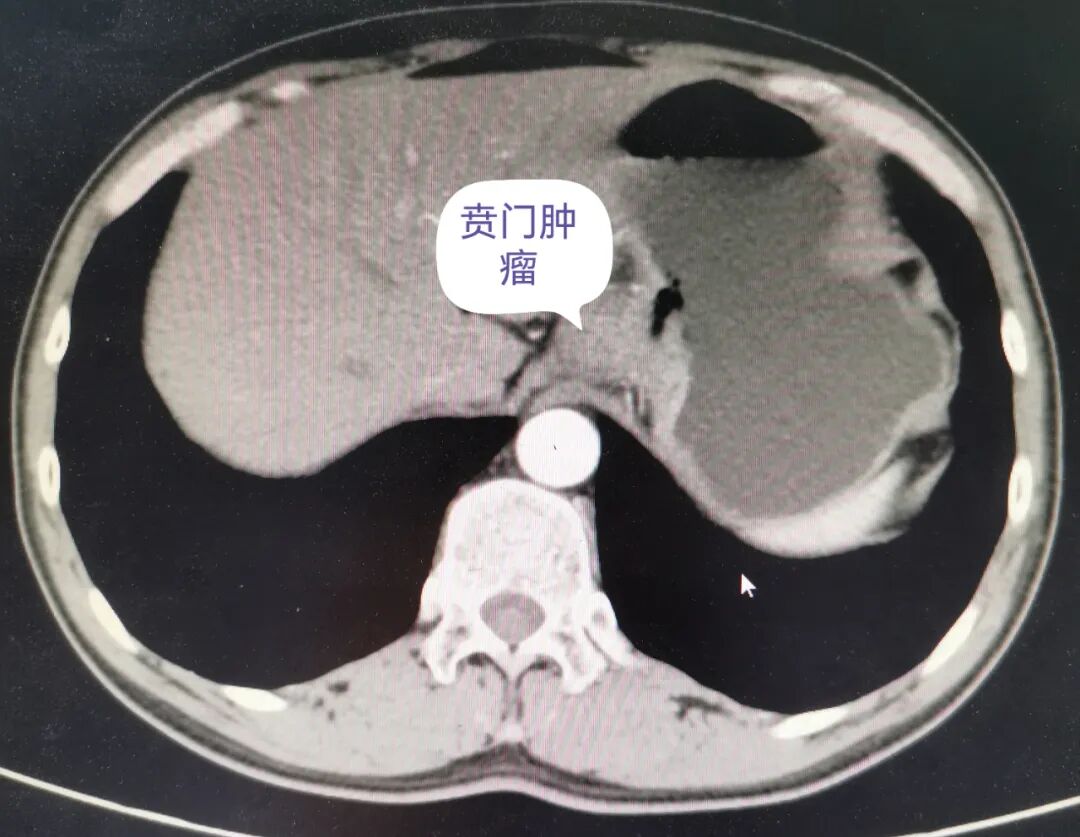

47岁的李大哥,出现间断进食哽噎感3周,经外院医生介绍慕名到长治二院胸外科就诊。胃镜检查提示:贲门和胃窦两处肿瘤。病检结果示:贲门、胃窦均系低分化腺癌。

术前钡餐造影和胸部CT影像

术前诊断:1.贲门低分化腺癌;2.胃窦低分化腺癌。

患者同时患上贲门和胃窦部两处高度恶性肿瘤,贲门是在胃的入口处,胃窦部接近胃的出口幽门处,手术方式只能行全胃切除,由于患者贲门肿瘤侵犯食管下段超过3cm,单纯经腹部手术食管下段肿瘤难以切除干净,必须采取胸腹部联合切口方能完成全胃切除+空肠食管吻合术。